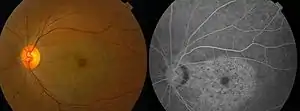

Chloroquine retinopathy[2]

With continued drug exposure, there is progressive development of a bilateral atrophic bull's-eye maculopathy and paracentral scotomata, which may in severe cases ultimately spread over the entire fundus, causing widespread retinal atrophy and visual loss.

Profound abnormalities detected with visual field and multifocal electroretinography testing can be observed in the presence of a normal retinal appearance. Retinal examinations are advised for documentation, but visible bull's-eye maculopathy is a late change,[6] and the goal of screening is to recognize toxicity at an earlier stage. Annual screening should begin after 5 years (or sooner if there are unusual risk factors).[5]